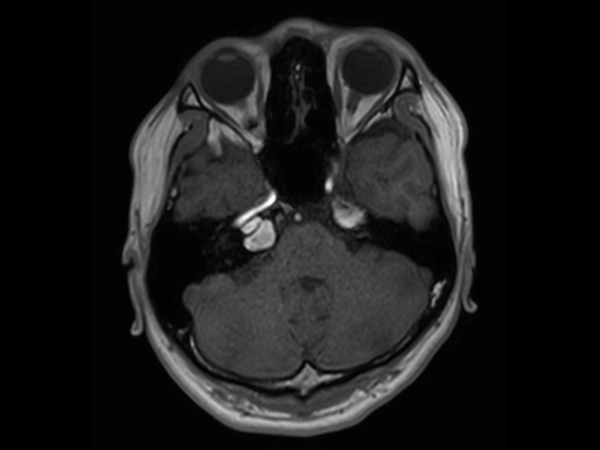

Patient with an IAC lesion. Comparing different DWI methods (EPI, TSE, ZOOM). Compressed SENSE is added to all TSE sequences to decrease scan times, thereby shortening the time the patient has to spent in the magnet. The dS Head 32ch coil is used to enhance image quality.

T1w SE